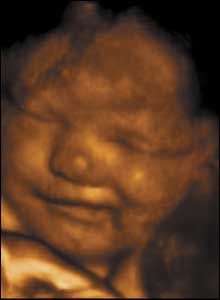

34 weeks gestation. 34cm from crown to rump.

8 of 10

While newborns do not smile until 4-6 weeks after birth, babies in the uterus do. Maybe because the uterus is warm, comfortable, and shielded from loud noise and bright light.